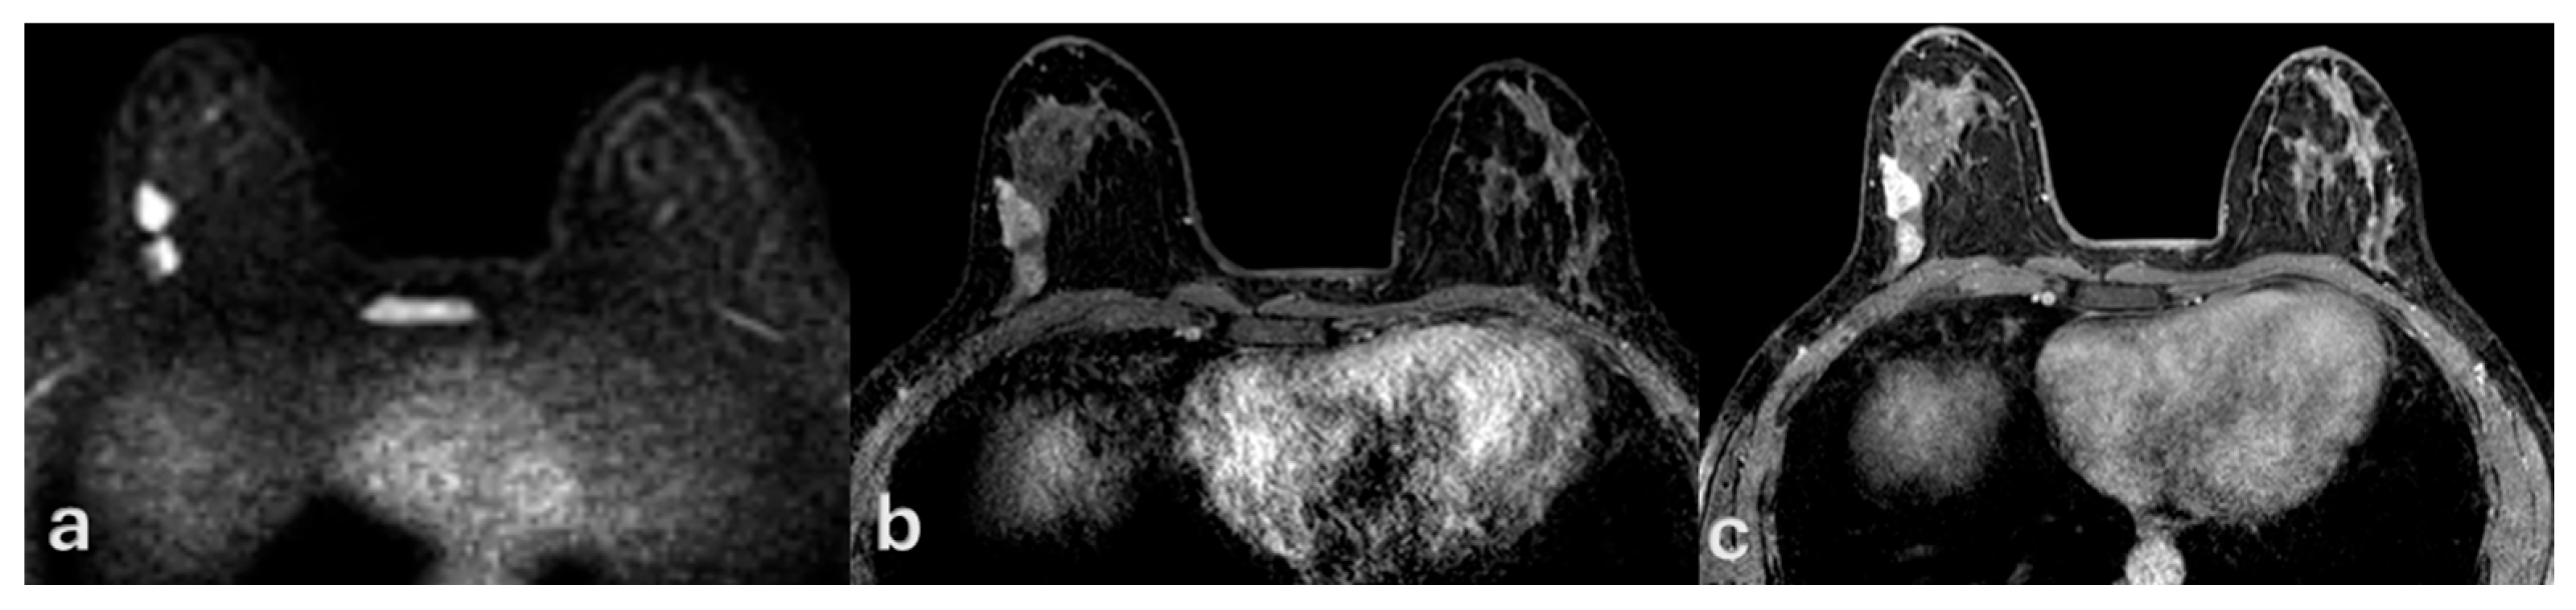

Multimodal Imaging of Ductal Carcinoma In Situ: A Single-Center Study of 75 Cases

3. Results